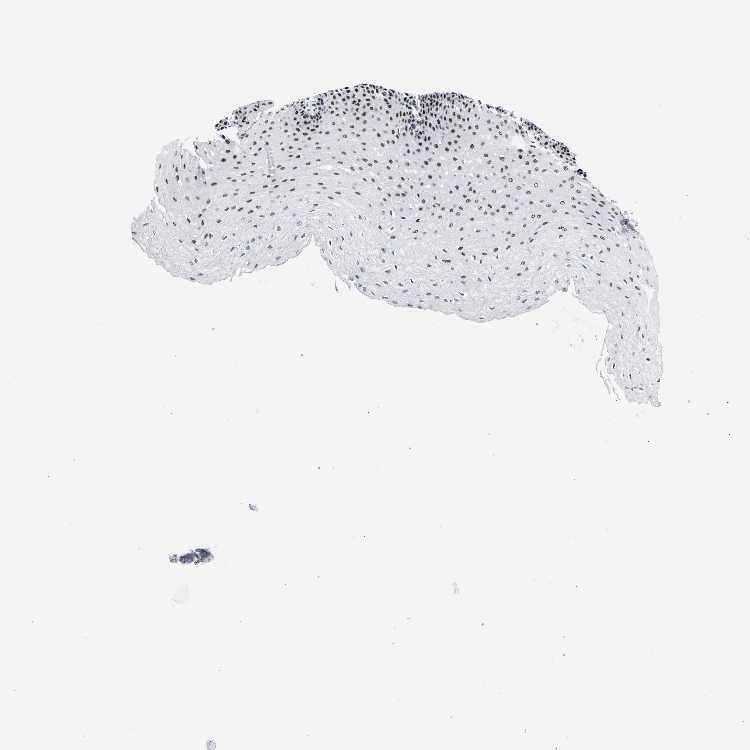

ESOPHAGUS - Antibody stainingi

Antibody staining in the annotated cell types in the current human tissue is reported as not detected, low, medium, or high, based on conventional immunohistochemistry profiling in selected tissues. This score is based on the combination of the staining intensity and fraction of stained cells.

Each image is clickable and will lead to virtual microscopy that enables deeper exploration of all samples and also displays staining intensity scores, fraction scores and subcellular localization as well as patient and tissue information for each sample.

Antibody HPA019907Antibody HPA019943Antibody CAB072827

Squamous epithelial cells HighHighHigh